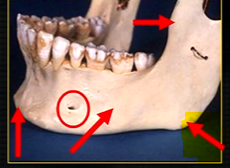

mandible - the lower jaw

mental foramina

dense bony prominence of the external oblique ridge

mandible varies in cross sectional thickness

left hand side of the mandible buccal surface has been removed

roots of the teeth protrude in the underlying trabecular bone

inferior dental nerve

mental nerve - coming out of the mental foramen

reveals honeycombed pattern of trabecular bone

dense outline of the individual sockets of the teeth

cortical bone which forms the lower border

mental foramen - black radiolucency - near 1st and 2nd premolars

sockets of the teeth are represented by thin, white, opaque lines → ‘ lamina dura’

dense, white, radiopaque line → dense bone of mylohyoid ridge

underneath mylohyoid ridge - looks more radiolucent → this is due to the lingual indentation of submandibular fossa

dense cortical bone of the lower border